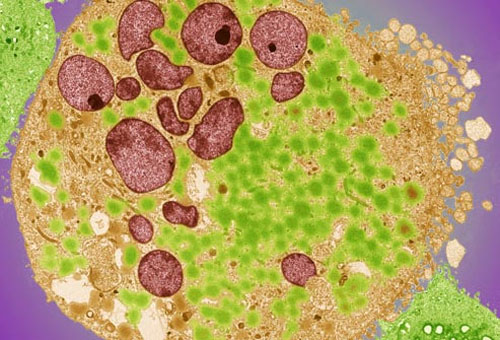

Các loại ung thư bàng quang

Các loại chính của ung thư bàng quang được đặt tên theo loại tế bào phát triển thành ung thư. Phổ biến nhất là ung thư tế bào chuyển tiếp - bắt đầu trong các tế bào lót bên trong bàng quang. Ung thư biểu mô tế bào vảy và ung thư tuyến là ít phổ biến hơn.

Có 3 loại ung thư bàng quang